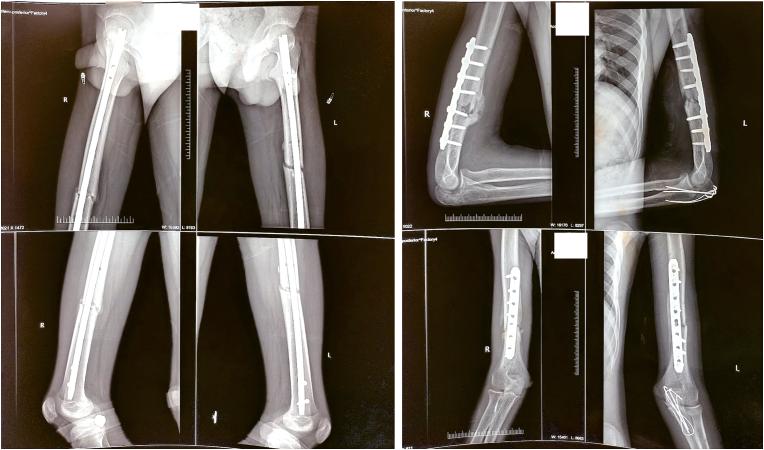

A 19-year-old man had an accidental fall from the 2nd floor and sustained multiple injuries. On radiological evaluation, the patient had symmetrical quadruple limb involvement with bilateral humerus shaft, bilateral olecranon, bilateral femur shaft, and bilateral patella fractures. The patient was actively managed using damage control orthopaedics, and a sequence of skeletal fixation was planned based on the hemodynamic stability and periodical serum lactate assessment. Symmetrical quadruple limb fractures are very rare, which could be associated with higher mortality. A meticulous clinical evaluation, periodical blood parameter assessment and strict adherence to the principles of damage control orthopaedics can be conducive to prevent life-endangering complications.

一名 19 岁男子从二楼意外坠落,多处受伤。影像学评估显示,患者四肢对称性受累,双侧肱骨干、双侧尺骨鹰嘴、双侧股骨干和双侧髌骨骨折。患者采用损伤控制骨科积极治疗,根据血流动力学稳定性和定期血清乳酸评估,计划进行一系列骨骼固定。四肢对称性骨折非常罕见,但可能与更高的死亡率相关。仔细的临床评估、定期的血液参数评估和严格遵循损伤控制骨科的原则有助于预防危及生命的并发症。